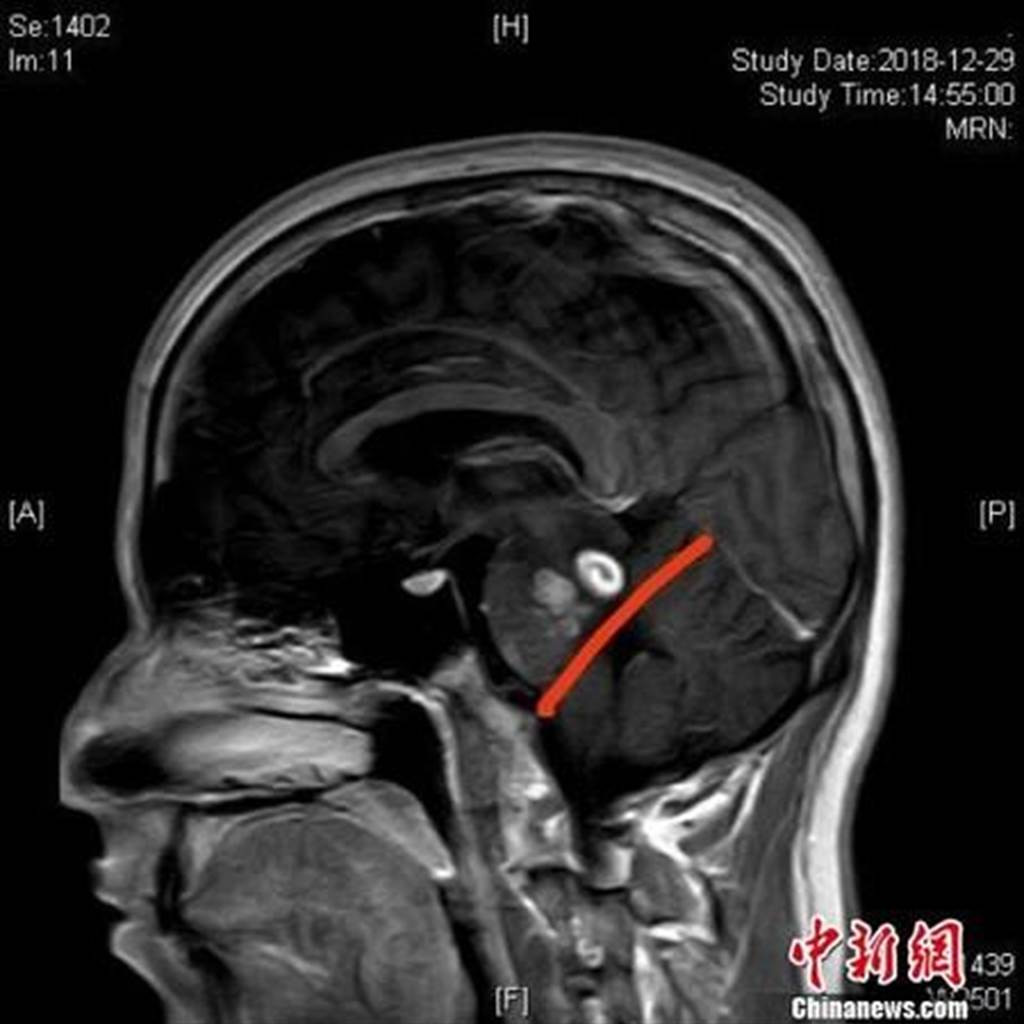

Nghi ngờ chồng trúng gió chuyển nặng, người vợ lập tức đưa chồng đến bệnh viện để khám chữa. Mới đầu, khi khám lâm sàng, các bác sĩ nghĩ rằng người đàn ông bị đột quỵ. Thế nhưng sau khi có kết quả chụp cộng hưởng từ MRI phần đầu, các bác sĩ nhận thấy mọi thứ đều bình thường và có khả năng bị nhiễm ký sinh trùng phần đầu.

Sau đó, bác sĩ lấy máu của người đàn ông để làm xét nghiệm. Cuối cùng, họ xác nhận, phần đầu của bệnh nhân đã bị nhiễm ký sinh trùng.

trường hợp nhiễm ký sinh trùng này rất đặc biệt, bác sĩ vô cùng tò mò về nguyên nhân nhiễm bệnh. Sau khi tìm hiểu, bác sĩ được biết, trước khi phát bệnh, người đàn ông đã sử dụng phương thuốc dân gian, ăn ếch sống để chữa bệnh về xương khớp. Chẳng ngờ, bệnh xương khớp không khỏi, anh còn bị nhiễm ký sinh trùng.

Theo các bác sĩ, nhiễm ký sinh trùng ở phần đầu vô cùng nguy hiểm. Không chỉ đau đầu, tay chân còn trở nên yếu đuối, vô lực, không thể kiểm soát được, mất khả năng ngôn ngữ. Trong trường hợp nghiêm trọng, bệnh nhân có thể bị tăng huyết áp nội sọ, dẫn đến tử vong.